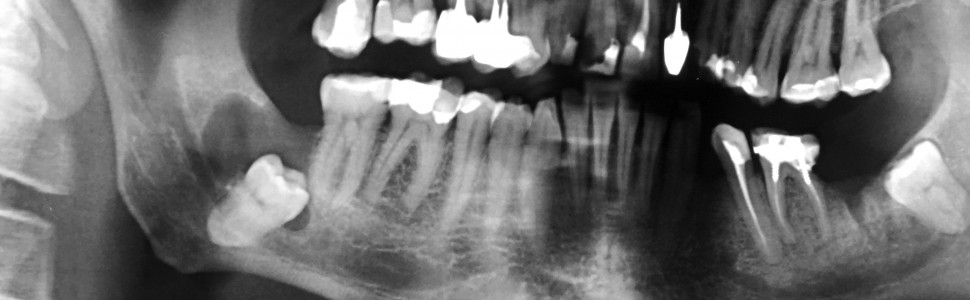

Torbiel zawiązkowa jest jedną z najczęstszych zmian w obszarze szczękowo‑twarzowym. Zazwyczaj jest związana z zatrzymanym zębem trzonowym trzecim żuchwy. Pacjenci najczęściej nie zgłaszają żadnych dolegliwości, gdyż rozwój zmiany jest przeważnie bezobjawowy. Torbiel zawiązkowa jest wykrywana przypadkowo na przeglądowych zdjęciach rentgenowskich. Całkowite wyłuszczenie torbieli jest postępowaniem z wyboru. W pracy przedstawiono przypadek 51 ‑letniego pacjenta z torbielą zawiązkową żuchwy związaną z zatrzymanym zębem 48.

Dentigerous cyst is one of the most common lesions in the maxilla ‑facial area. It is usually associated with impacted mandibular third molars. Patients usually do not report any complaints, because the growth of the lesion is mostly asymptomatic. Dentigerous cyst is detected accidentally on routine radiographic images. Complete enucleation of the cyst is the treatment of choice. The study presents the case of 51 ‑year ‑old male patient with dentigerous cyst of mandible related with impacted tooth 48.